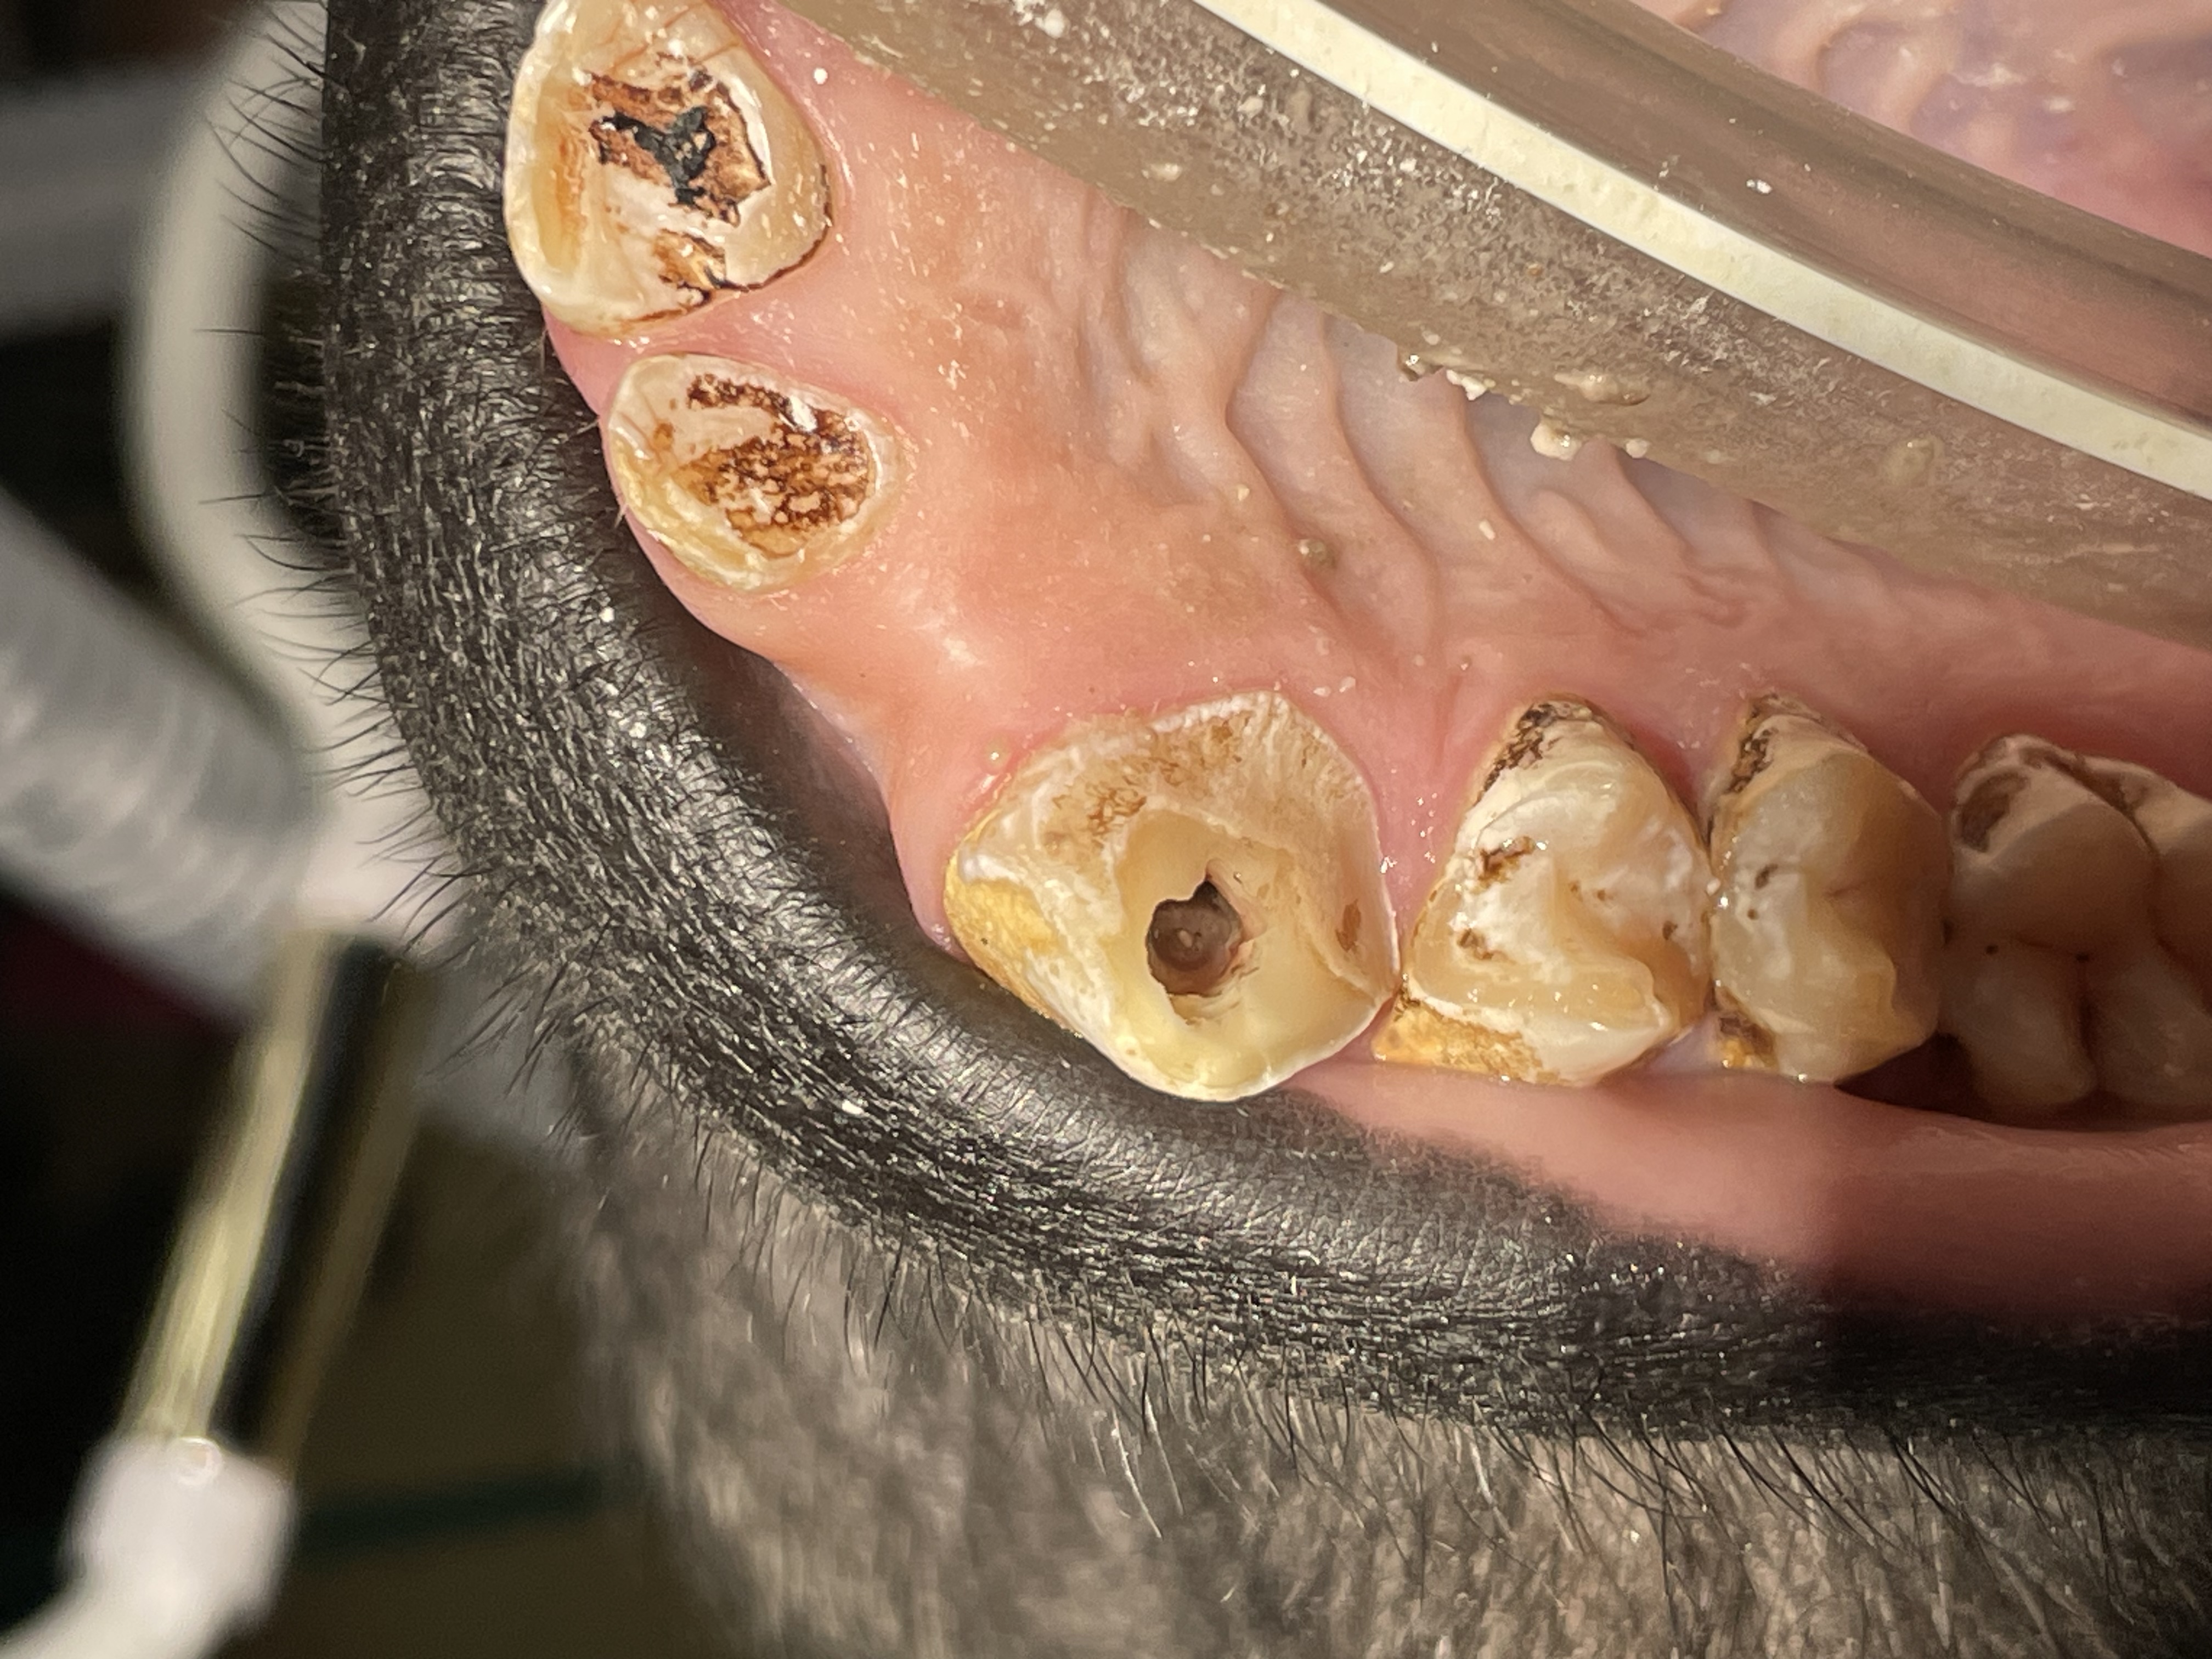

Enamel erosion throughout dentition due to chronic regurgitation/ingestion behavior

I have also encountered significant dental attrition due to bruxism in many primate species. The psychological stress of confinement certainly contributes to such habits. Again, zoo keepers are very aware of such issues and these are addressed in many effective ways. Another habit related to stress, regurgitation of food and reingesting it, causes very significant damage to the entire periodontium, leading to loss of teeth. See Dr. John Huffs' on treating Tino at Salt Lake City zoo. I examined Tino when he was young at our zoo. He already had the regurgitation habit then.